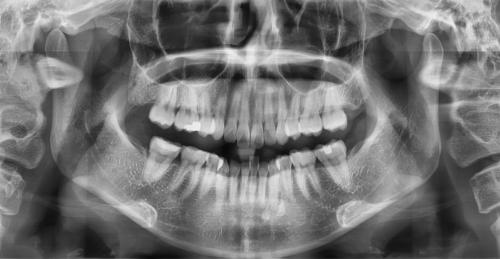

1. 파노라마 사진 ( 위아래 턱이 한꺼번에 나와서 사진 하나에 치아가 모두 찍히는 사진 )만 보며 설명 할 뿐 의사가 탐침으로 입 안을 살피지 않는 경우 패스합니다.

일단 엑스레이를 찍는 이유는 치아와 치아가 붙은 그 사이를 육안으로 확인하기 어려운 경우에 도움을 받으려고 찍거나 치아 뿌리의 상태를 확인하기 위해서 찍습니다.

치아 윗면이나 옆면은 직접 입 안을 살펴보고 탐침으로 건드려보고 하면 견적이 나옵니다.

게다가 파노라마 사진의 경우 이것만으로는 치아 사이의 충치를 완벽히 발견 할 수 조차 없습니다.

치아 사이의 충치를 제대로 확인하려면 교익 방사선 사진이 필요합니다.

( 추가: 파노라마 사진, 교익 방사선 사진 )

파노라마